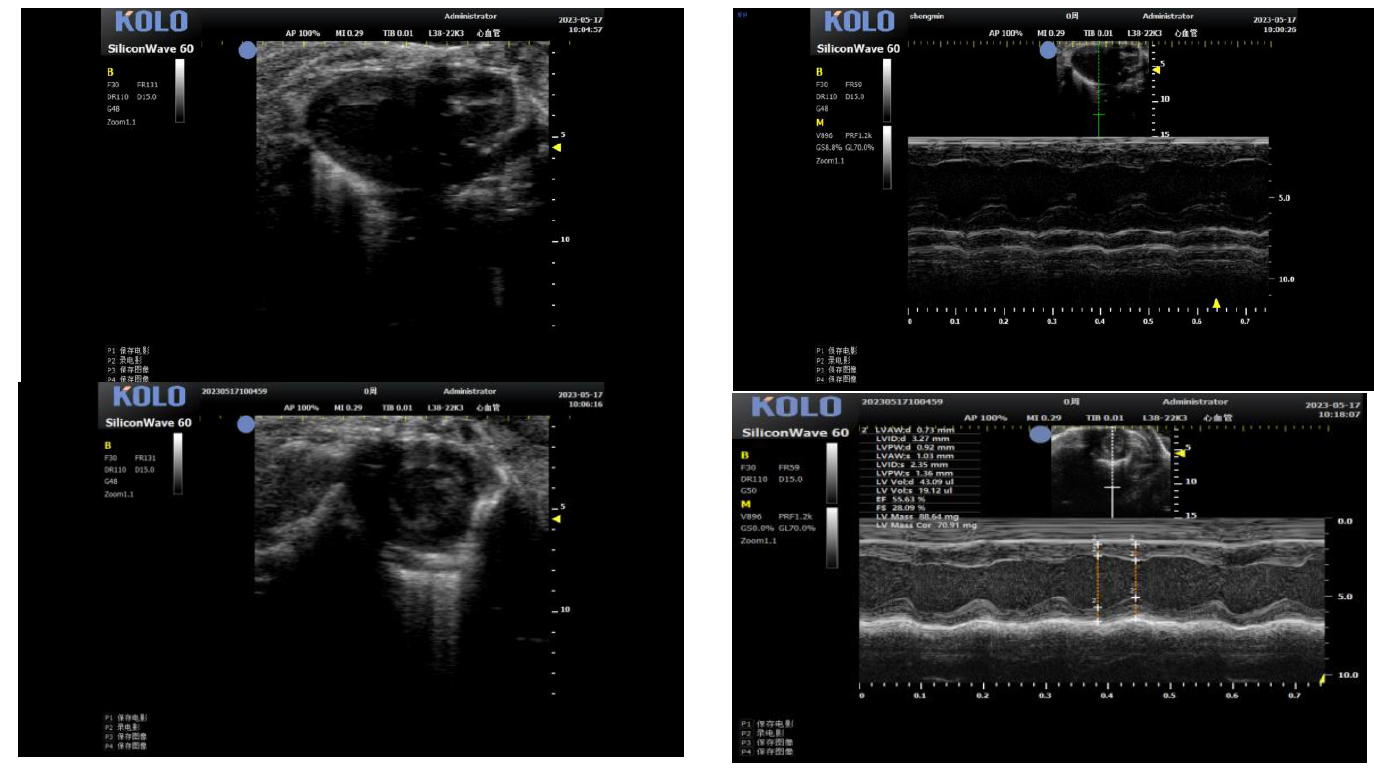

1. 小鼠心脏研究---左心室(长+短轴+M 超)